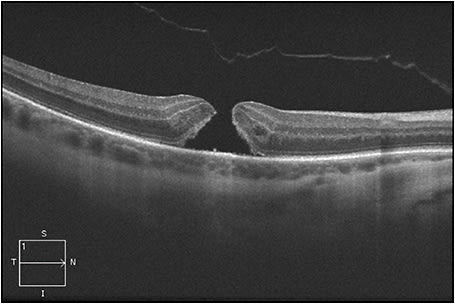

Figure 1 shows an eye in this series, with FTMH measuring 216 µm and concurrent focal VMT; this patient’s best-corrected Snellen VA was 20/70. Figure 2 shows VMT release following intravitreal ocriplasmin, with a decrease in VA to 20/200 at one week following injection. Figure 3 demonstrates an increase in FTMH size (now measuring 264 µm) at 12 days following injection.

Figure 3. An increase in FTMH size (now measuring 264 µm) occurred at 12 days following injection.